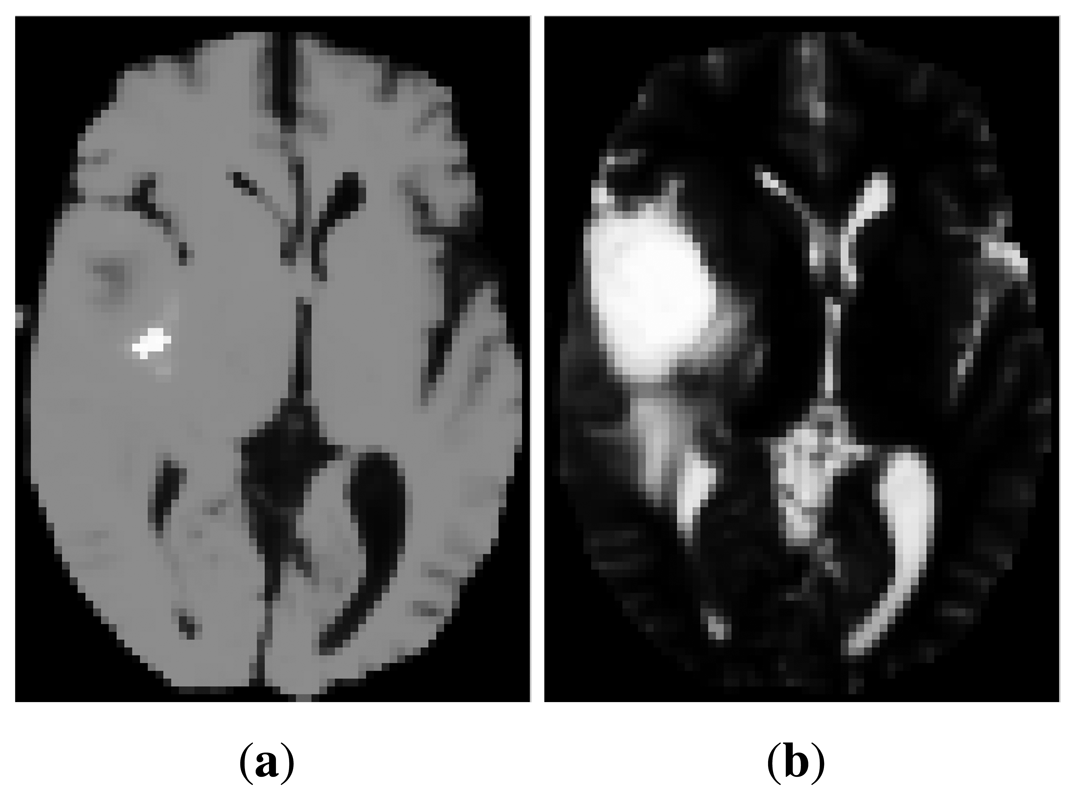

The purpose of multimodal image registration is to identify the geometric transformation that maps the coordinate system of one modality into another. Multimodal images have significant variations in their intensities, which makes it difficult to capture their structural similarities, thus increasing the difficulty of achieving accurate registration. As an illustration, Figure 1 shows corresponding slices of 3D multimodal images of a human head. While a T1 magnetic resonance (MR) image shows better anatomical detail (Figure 1a), T2 MR highlights pathological changes better (Figure 1b).

Recently, manifold learning techniques have begun to be applied for image registration [11], although most of the reported methods deal with monomodal data. The most common approach is to apply manifold learning to a population of monomodal images to extract information on the neighborhood structure of the data set (i.e., which images are close to each other) and, hence, confine the search of anatomically plausible transformations [12,13]. There are also a few works where a manifold learning method has been applied to each individual image separately in order to obtain a new representation, which can help in finding image correspondences. For example, Xu et al. [14,15] use Isomap or PCA to extract features, which are then passed to a neural network, whose outputs are the affine transformation parameters. Furthermore, in the context of rigid (but multimodal) registration, Wachinger et al. [6] employ Laplacian eigenmaps to generate a new set of features, which allows the use of monomodal similarity measures. This is justified because the Laplacian eigenmap can be considered a structural image descriptor, and hence, its appearance across modalities is similar. Nonetheless, there are cases for which the large intensity variations across the original images result in too different eigenmaps preventing from direct comparison. This is illustrated in Figure 2a,b. Other drawbacks are that Laplacian eigenmaps heavily depend on the density of the samples [16] and that an additional step of manifold alignment is required to ensure that the representations of image intensities are comparable across manifolds [6].